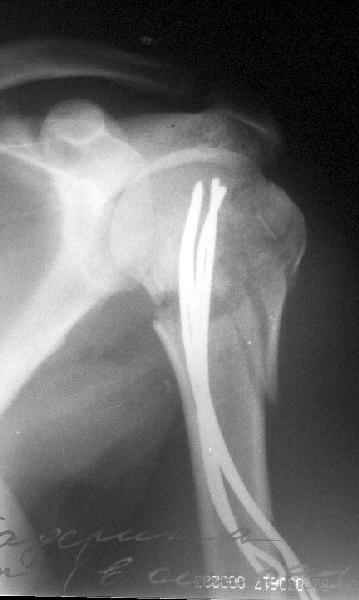

Здесь случай перелома-вывиха плеча, больному 56 лет, после "дважды" закрытой неудачной репозиции, опять же ургентно взяли в операционную, после полного общего обезболивания попытались сделать репозицию, и фиксацию провели спицами.

Больной находился в повязке, примерно напоминяющей косыночную, рекомендованы движения в локтевом суставе и маятниковые движения в плече, спицы удалены в три недели (были случаи миграции)

Больной амбулаторный, предупрежден на случай осложнения АВН головки.

Клинические снимки - 3 недели после операции

с уважением М. Беренштейн